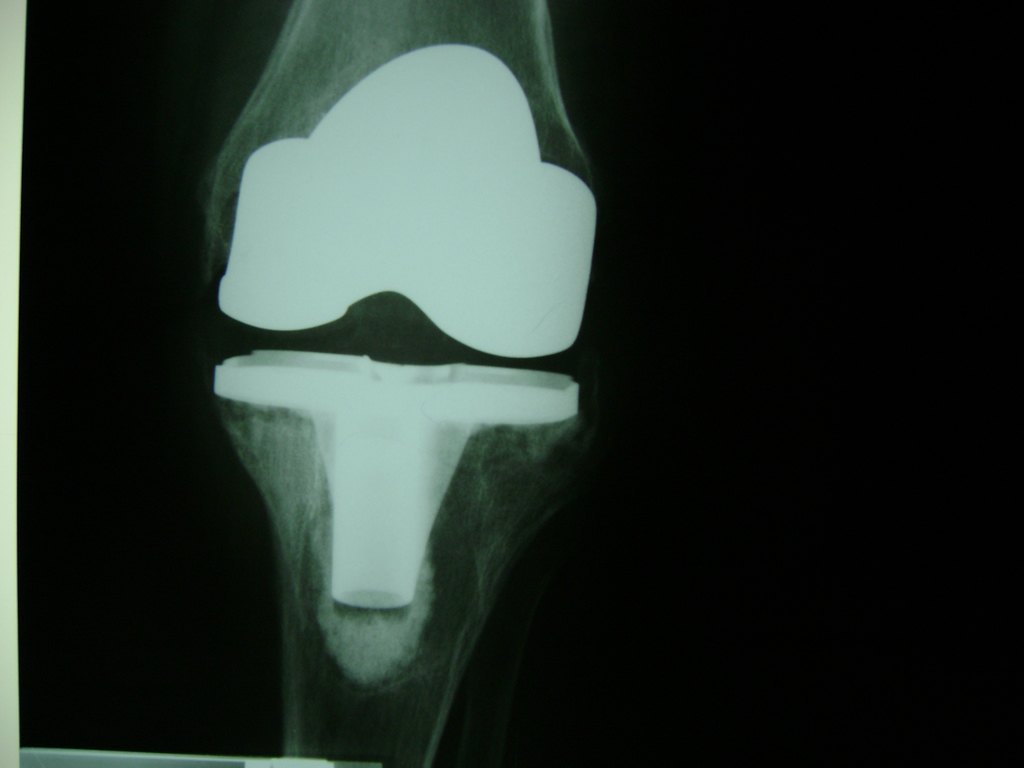

Cirugías de Rodillas